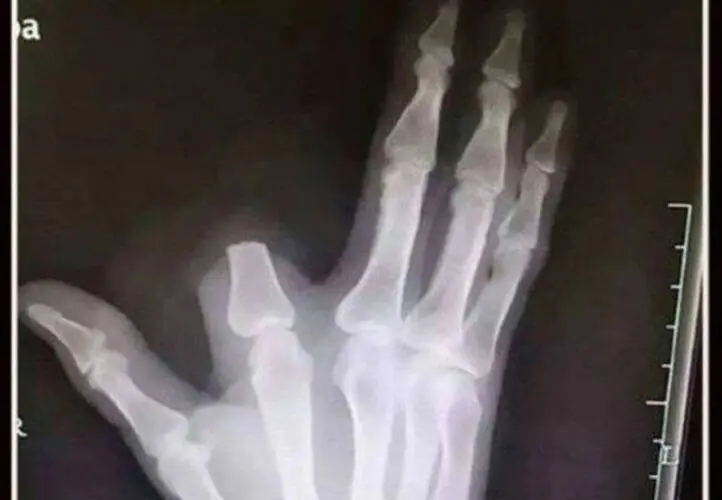

O dedo amputado ficou no local do incidente, o que impossibilitou qualquer tentativa de reimplante. A atitude do agricultor, embora motivada pelo medo e pela urgência da situação, acabou resultando em uma lesão permanente.